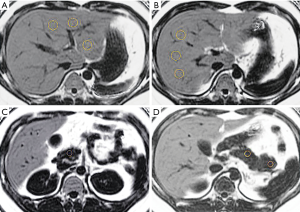

Measurement of hepatic and pancreatic PDFF

The MRI images were reviewed by a radiologist with more than 6 years of experience in abdominal imaging who was blinded to the clinical and biochemical data of all of the patients. The liver and pancreas PDFF levels were measured on the fat fraction maps using the workstation (AW 4.4, GE Healthcare). Hepatic PDFF levels were measured by placing 2 regions of interest (ROIs) each in the left and right lobes with an approximate ROI of 40–60 mm2. One ROI each in the head, body, and tail of the pancreas of approximately 10–15 mm2 was placed, and the PDFF of each ROI was measured. Then, the average liver and pancreas PDFF levels were calculated. All of the ROIs were surrounded by the tissue of interest to ensure that the ROIs were within the tissue of interest, avoiding major vessels, ducts, and collecting systems (Figure 2).